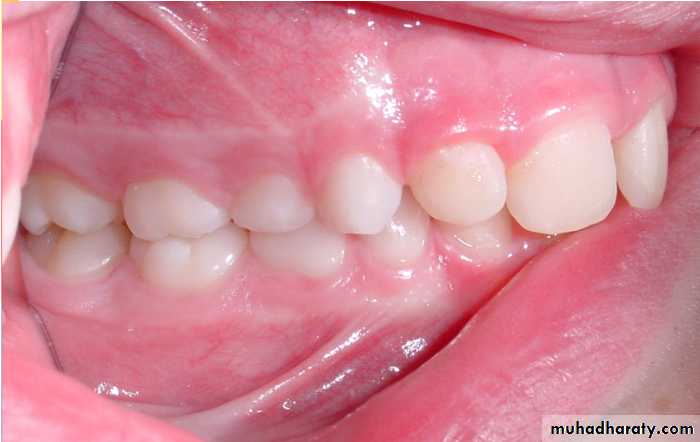

Keys to differentiating primary and permanent teeth:

Color primary teeth white and opaque

Size and contoursDepth of anatomy

Age of child

Location of teeth (counting)